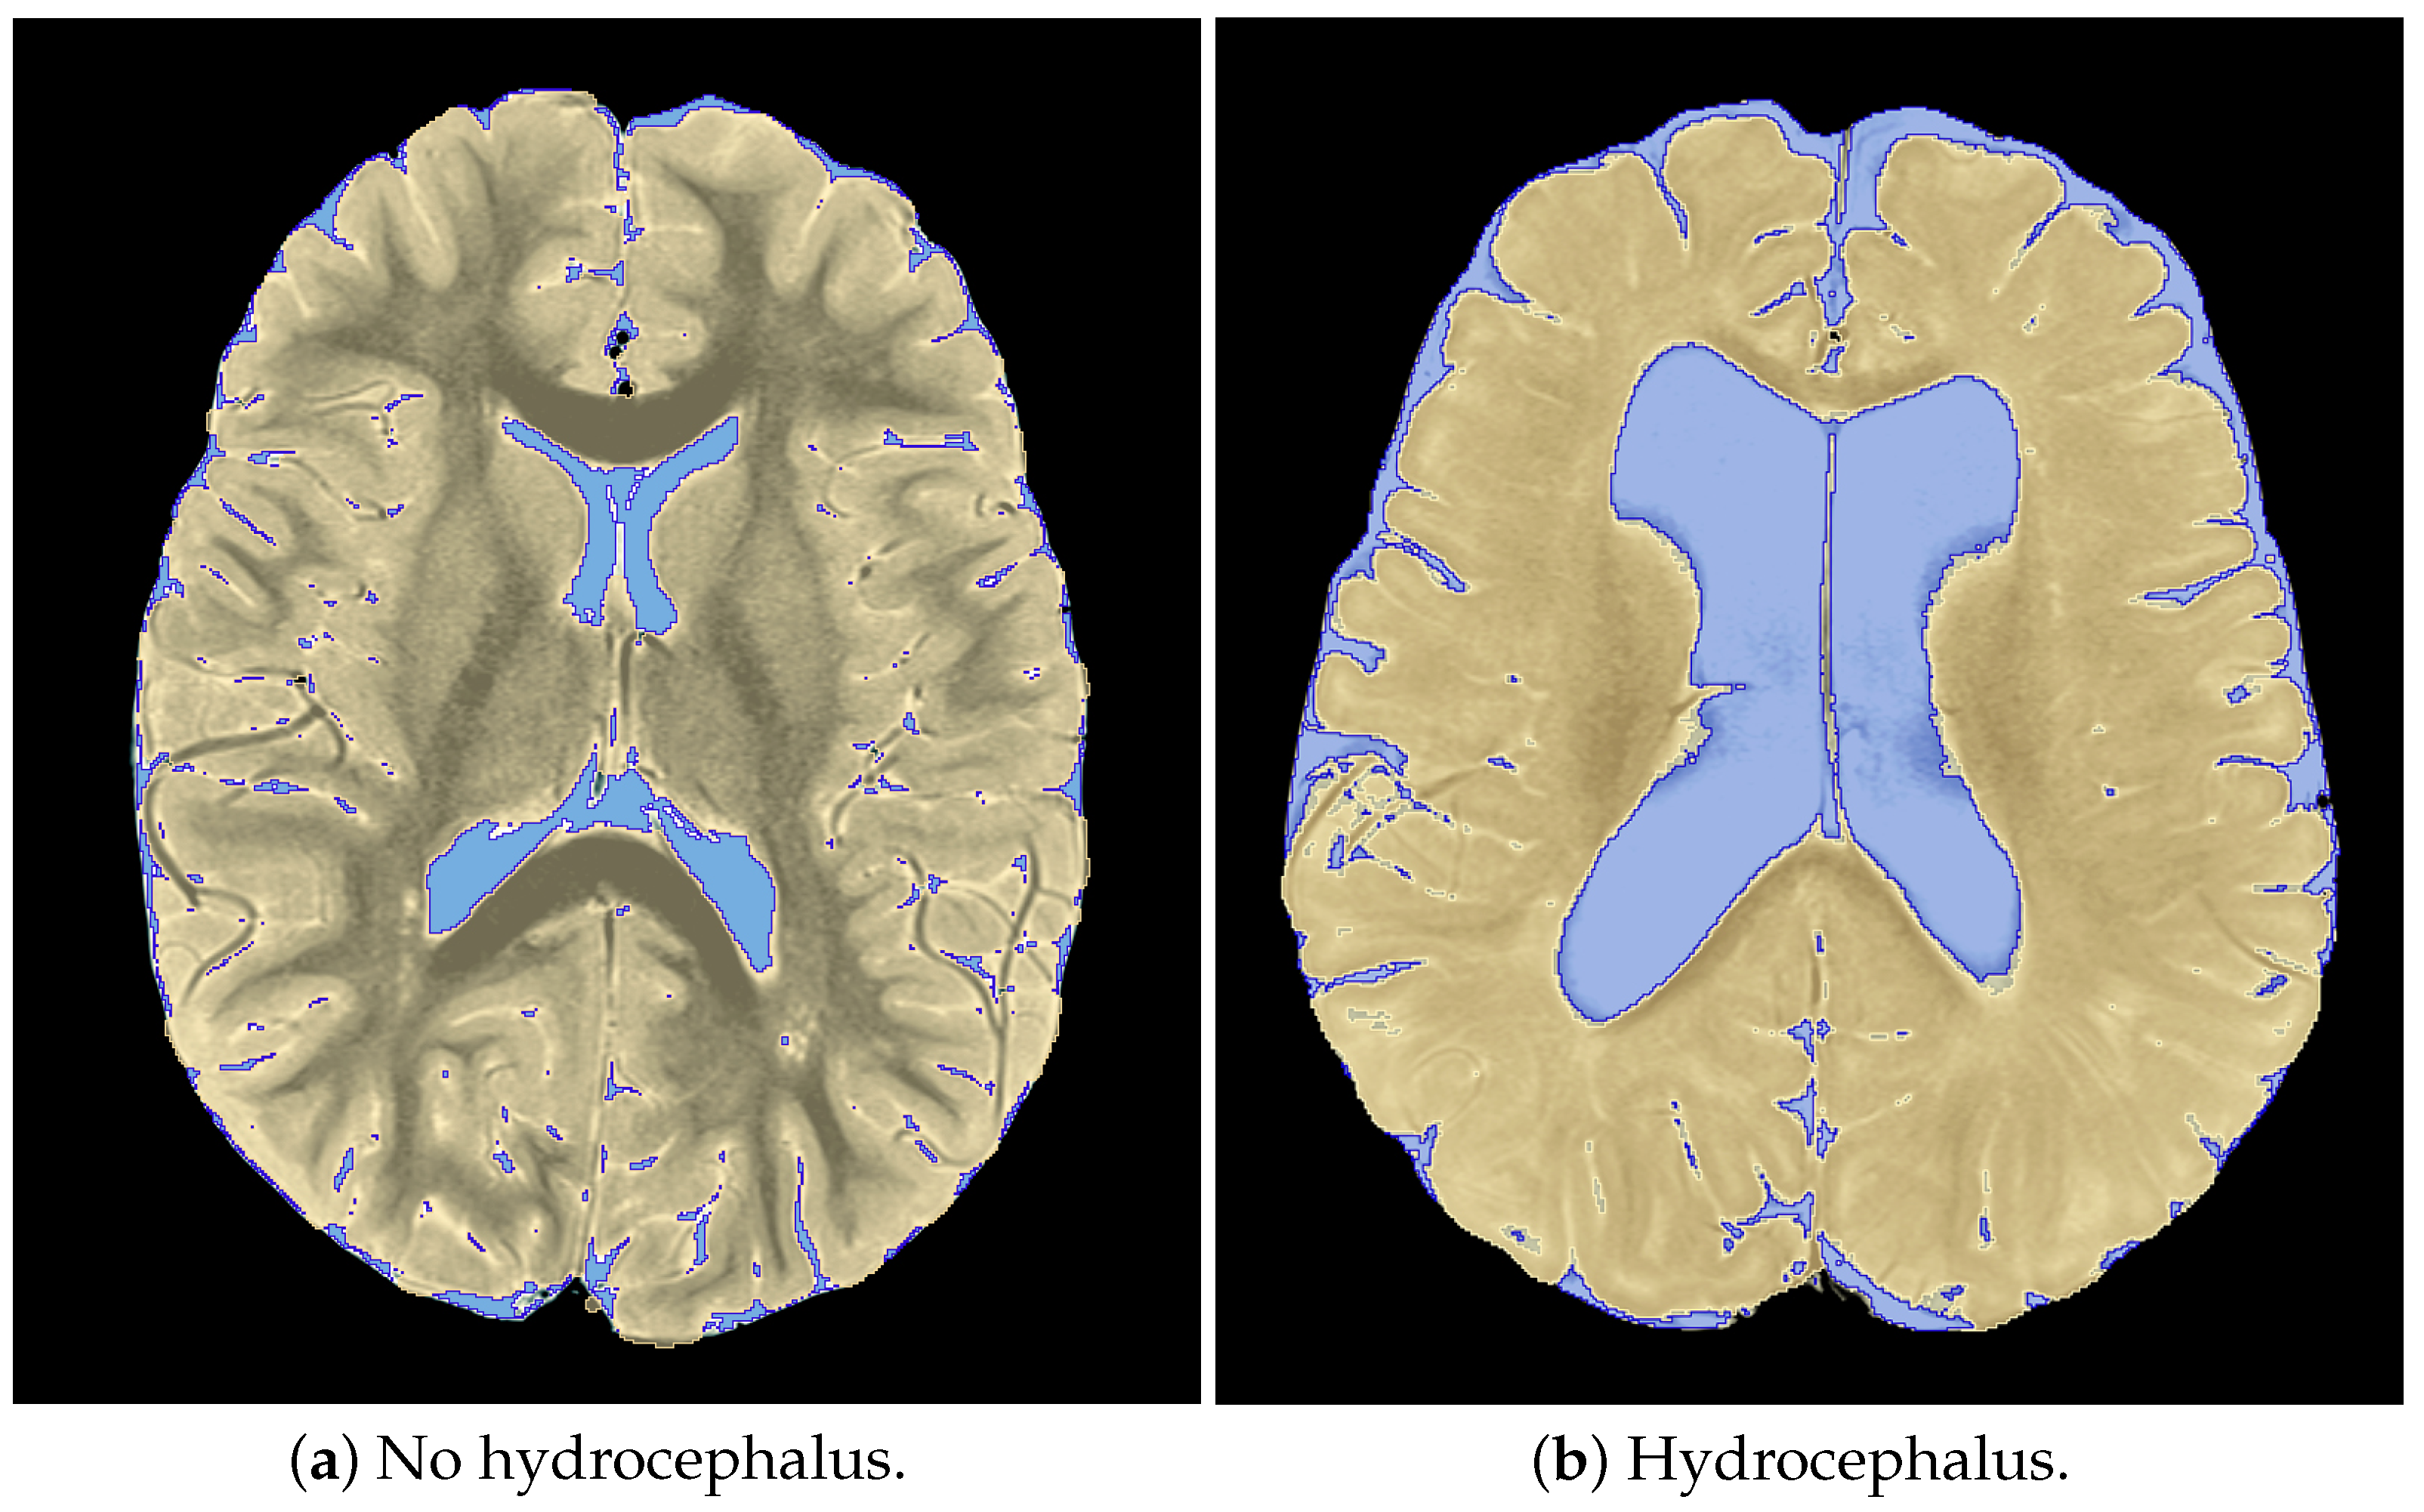

2.4. Subjective Hydrocephalus Rating